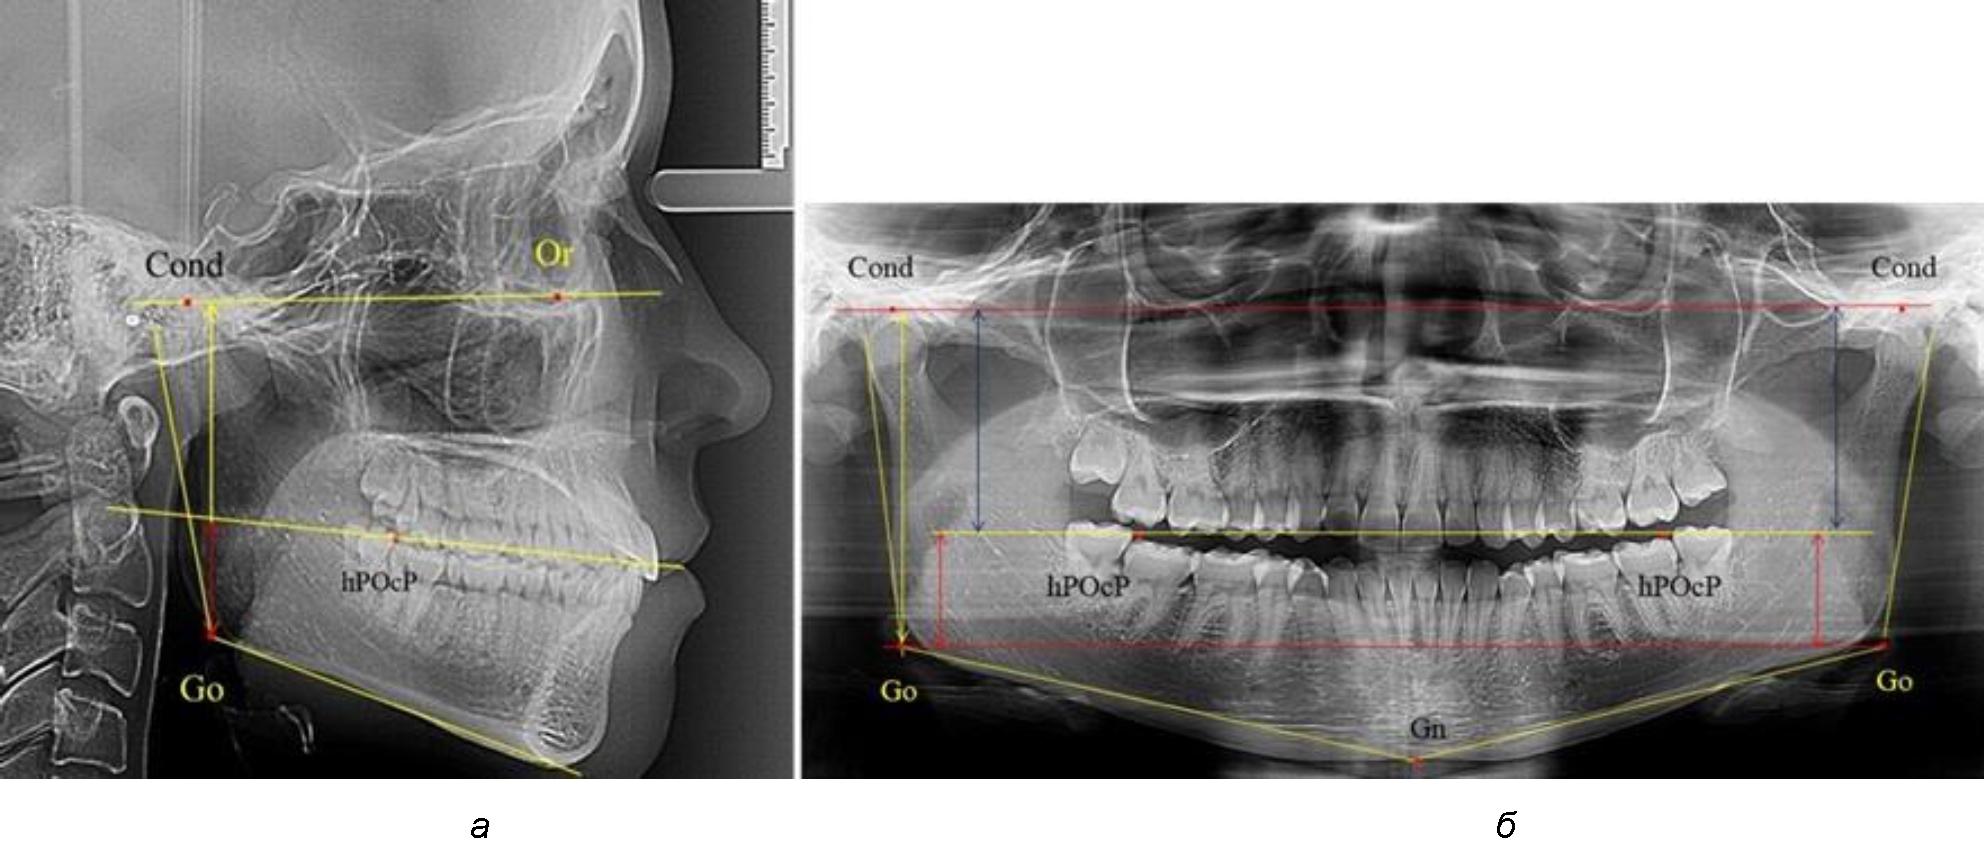

На боковых телерентгенограммах определяли положение верхней точки суставной головки Cond. Касательные линии к ветви и телу нижней челюсти пересекались в точке, которую в клинической практике обозначают как точка угла нижней челюсти или точка гонион Go. Точкой hPOcP обозначали дистальный бугорок нижнего второго моляра вблизи окклюзионного контура коронки, через нее от межрезцовой точки проводили окклюзионную линию, ее продолжали до задней части ветви челюсти. Высоту ветви измеряли как расстояние от угла нижней челюсти до вершины суставной головки Go-Cond. Общую высоту ветви условно делили на 2 части, ее границей служила окклюзионная линия. Верхнюю часть обозначали как окклюзионно-суставная, а нижнюю – как окклюзионно-гониональная.

На ортопантомограмме использовали аналогичные суставные точки Cond на каждой стороне, их соединяли между собой суставной линией Cond-Cond.

Касательная к ветви нижней челюсти соединяла выступающие точку. При построении касательной к телу челюсти проводили в обе стороны линии от точки Gn, расположенной в нижней центральной части подбородочного симфиза, до выступающей нижней точки угла челюсти. Касательные линии при пересечении определяли конструктивную точку гонион Go. Соединение гониональных точек определяло положение гониональной линии Go-Go. При соединении окклюзионных точек hPOcP получали окклюзионную горизонталь (рис. 1). Измеряли расстояние между горизонталями в области ветвей нижней челюсти. Статистический анализ проводили в программе Microsoft Excel. Составляли вариационные ряды с последующим расчетом среднего значения, стандартного отклонения и ошибки среднего ±m. Также оценивали максимальные и минимальные значения величин. Определи относительные величины соотношения верхней и нижней частей ветви нижней челюсти.

Рис. 1. Метод измерения высоты ветви нижней челюсти на телерентгенограмме (а) и ортопантомограмме (б)